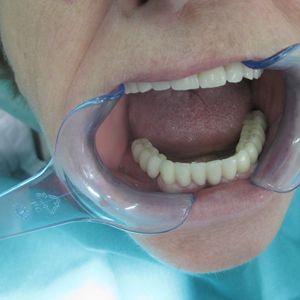

Prosthetic rehabilitation: once osseointegration is complete, an abutment and permanent crown, bridge, or denture is placed on the implant. Prosthetic rehabilitation on implants is our core specialty and is key to the long-term success of the treatment.

Denture stability: implants provide a secure anchor for dentures, eliminating problems with rocking and uncomfortable adhesives.

Improved quality of life: patients with implants enjoy food again, speak clearly, and feel confident in everyday life.